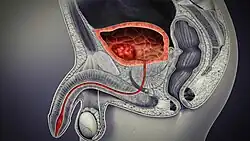

In humans, the bladder is a hollow muscular organ situated at the base of the pelvis. In gross anatomy, the bladder can be divided into a broad fundus (base), a body, an apex, and a neck.[5] The apex (also called the vertex) is directed forward toward the upper part of the pubic symphysis, and from there the median umbilical ligament continues upward on the back of the anterior abdominal wall to the umbilicus. The peritoneum is carried by it from the apex on to the abdominal wall to form the middle umbilical fold. The neck of the bladder is the area at the base of the trigone that surrounds the internal urethral orifice that leads to the urethra.[5] In males, the neck of the urinary bladder is next to the prostate gland.

In males, the prostate gland lies outside the opening for the urethra. The middle lobe of the prostate causes an elevation in the mucous membrane behind the internal urethral orifice called the uvula of urinary bladder. The uvula can enlarge when the prostate becomes enlarged.

The bladder is located below the peritoneal cavity near the pelvic floor and behind the pubic symphysis. In males, it lies in front of the rectum, separated by the rectovesical pouch, and is supported by fibres of the levator ani and of the prostate gland. In females, it lies in front of the uterus, separated by the vesicouterine pouch, and is supported by the elevator ani and the upper part of the vagina.[10]

The human bladder derives from the urogenital sinus, and it is initially continuous with the allantois. The upper and lower parts of the bladder develop separately and join around the middle part of development.[7] At this time the ureters move from the mesonephric ducts to the trigone.[7] In males, the base of the bladder lies between the rectum and the pubic symphysis. It is superior to the prostate, and separated from the rectum by the recto-vesical pouch. In females, the bladder sits inferior to the uterus and anterior to the vagina; thus its maximum capacity is lower than in males. It is separated from the uterus by the vesico-uterine pouch. In infants and young children the urinary bladder is in the abdomen even when empty.[18]